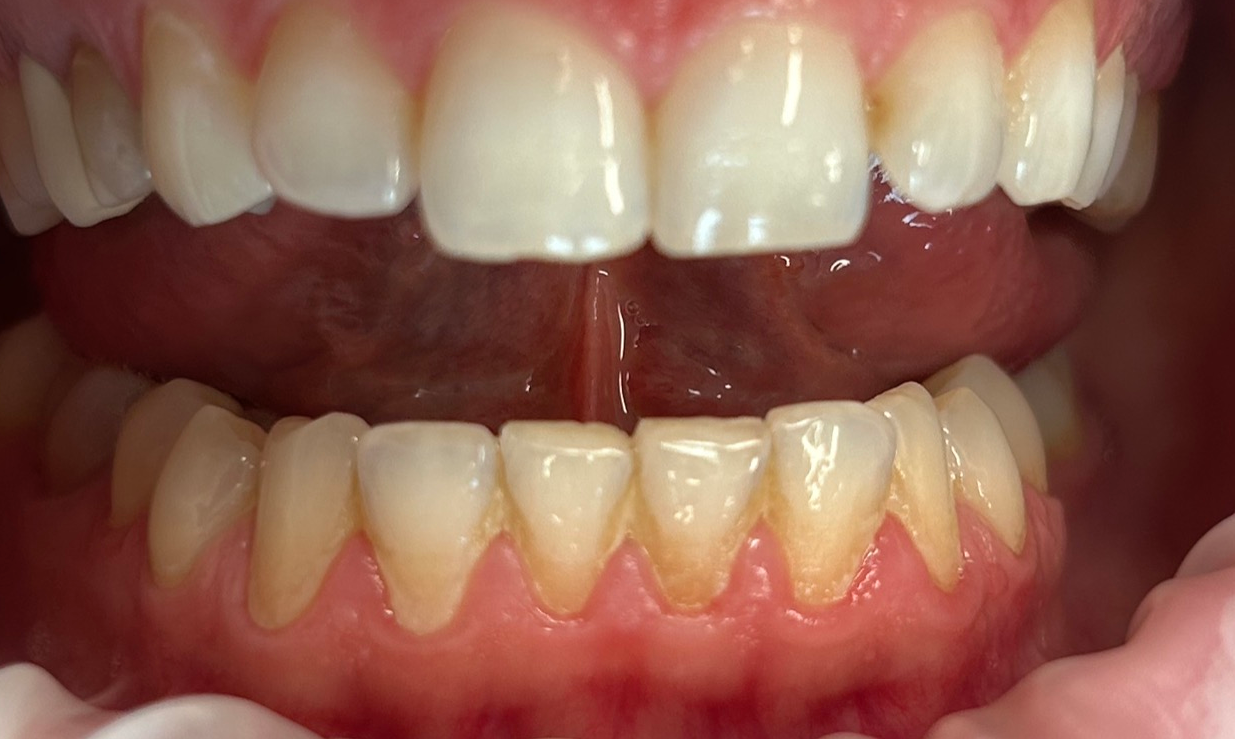

Zaprezentujemy serię poruszających historii pacjentów, którzy zdecydowali się na kompleksowe leczenie dentystyczne. Od przypadków zaawansowanej próchnicy, przez wypadki, które wymagały rekonstrukcji zębów, po pacjentów marzących o hollywoodzkim uśmiechu dzięki zastosowaniu licówek – każda historia jest dowodem na to, jak nowoczesna stomatologia może odmienić życie.

Skupimy się na innowacyjnych technologiach i metodach leczenia stosowanych w naszej klinice, które sprawiają, że te metamorfozy są możliwe. Od cyfrowego projektowania uśmiechu (DSD), przez ortodoncję i implanty, po zaawansowaną chirurgię szczękowo-twarzową. Omówimy, jak te techniki pracują razem, aby osiągnąć najlepsze wyniki.